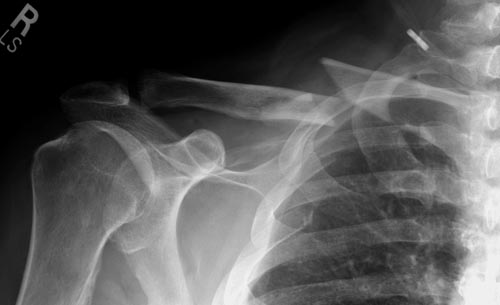

Болезненные ложные суставы надо оперировать, и здесь представлен случай

свежего болезненного ложного сустава, оперированного через 4 месяца.

Освобожден средний фрагмент и боковая компрессия лагированием, фиксация

пластиной..